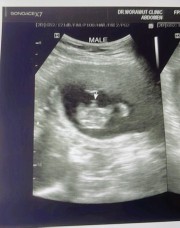

บ้านนี้ เห็นแบบนี้ค่ะแม่ หมอว่าน่าจะผู้ชาย รอซาวยืนยันอีกที วันที่25 นี้จ้า

คล้ายๆกันเลยคะ บ้านนี้หมอบอกว่าได้ผู้ชาย👶🏻

คล้ายกันเลยค่ะ บ้านนี้หมอฟันธงเลยค่ะ🤣🤣

เหมือนจะชัดเลยค่ะ ผู้ชาย😂😂😂